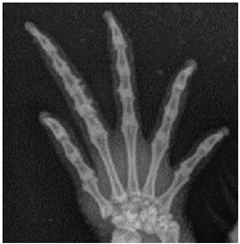

For this study, exclusively skeletal structures were examined. Four different structures (femur, ribs, vertebra, and phalanx) were chosen based on different bone architecture or features such as the differentiation of bone to soft tissue and surroundings (Table 3). The femur was essentially chosen to evaluate the differentiation between corticalis and spongiosa, joint structures were evaluated based on the left front phalanx, and the last left rib was used to further evaluate the details and structure of the corticalis. For each anatomical structure, four different characteristics (Table 3) were evaluated using a four-scaled scoring system, ranging from 1 (optimal evaluation) to 4 (insufficient evaluation). Scoring systems were used according to the modification of Körner, M. et al. [25] (Table 4).

In the present study, different skeletal structures of varying thickness and structure were used to have a broader spectrum of differences such as the transition from spongiosa to corticalis (femur, criterion 1) or demarcation to the joint (phalanx, criterion 2). Visceral structures were not assessed due to the use of dead bodies and the general challenge of assessing visceral structures with digital radiography in reptiles [2,9]. Visual grading characterizing (VGC) analysis was used and is recommended to evaluate the performance of different radiography systems. By using visual grading, anatomical criteria can be evaluated objectively with a link to clinical interpretation. Still, bias can occur, in this case primarily regarding the reviewers rating the systems. The reviewers were chosen regarding their experience with radiography in reptile species with a minimum of two years of experience in regularly evaluating radiographs in a specialized clinic. A training session was conducted beforehand to reduce divergence in scoring and achieve standardization. However, scores did differ significantly from each other (except for reviewer 1 compared to 4), showing the importance of subjectiveness and individual experience by different human beings even when using a scoring system. The disadvantages and advantages of VGC analysis have already been described in other studies such as Tebrün, W. et al. [13], Båth, M. et al. [29], and Månsson, L. G. [30]. Despite a lack of agreement in scores, the tendency with which the reviewers did score the criteria was the same. Therefore, assessments were significantly correlated for all criteria and all reviewers. These correlations prove the validity of the method, as the interpretation of the study results exclusively relies on the comparison of the scores between the system and dosages.

4.3. Effect of Dose Reduction

Data showed that in every system, a dose reduction led to significantly worse scores for most of the criteria, especially in the “double” reduction from 100% to 25%. Regarding the criteria, the vertebra seems to be the most sensitive structure with significantly worse scores after every reduction with each system used. In contrast, the ribs showed the least influence of the dose reduction, only receiving decreased scores after a reduction of 25%. The effect of dose reduction for the criterion femur varied. In the ribs and femur, the reviewers had to evaluate the differentiation between the bone, whilst in the criteria for vertebra and phalanx, the demarcation to the surrounding tissue and joint space was addressed. The vertebra and phalanx are much more delicate structures than the femur and rib, indicating a possible greater impact of dose reduction on smaller structures. In particular, the joint space with a fine surface and superimpositions of other structures could therefore be more affected than more solid structures such as the femur. The ribs are much more delicate than the femur, impeding the evaluation of this criterion and possibly leading to a greater impact in dose reduction, again indicating a greater influence on smaller structures. In contrast, the femur showed the best scores, indicating that the thicker and bigger the structure, the higher the chance of being able to evaluate variances.